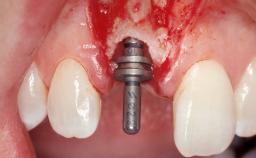

A 30-year-old female patient had lost tooth 21 and was referred to our clinic for consultation and treatment. Due to advanced apical infection, tooth 21 had been extracted two months earlier at another clinic and an acrylic-resin tooth had been bonded to the adjacent teeth. The patient desired implant treatment to avoid any damage to the adjacent natural teeth. While the patient had no history of any systemic disorder, she was a heavy smoker and exhibited medium to advanced periodontitis in the entire jaw. After the initial treatment to achieve a pocket probing depth of less than 4 mm and no bleeding on probing, a decrease in the height of the papillae mesial and distal to the extraction site and overall gingival recession were observed.

| # of Implants | 1 |

| Type of Implants | One-Piece|Reduced-Diameter |

| Attachment | One-Piece|Reduced-Diameter |

| Placement Protocol | Early or late implant placement |